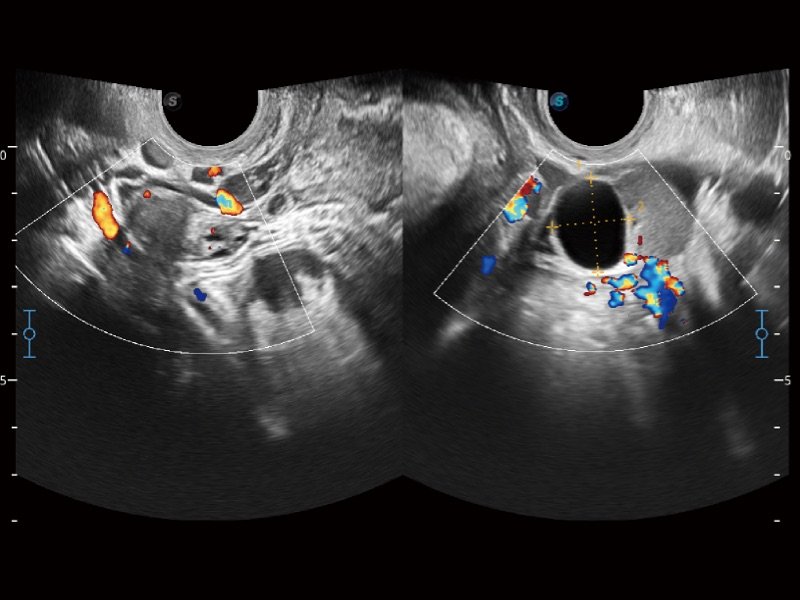

Contrast Imaging

Die Kontrastmittel sorgen für eine starke Signalreflexion, so dass schwer einsehbarer Blutfluss besser dargestellt werden kann. Regelt den Schalldruck und bietet eine vielversprechende Bildqualität bei geringerer Wirkstoffdosis.